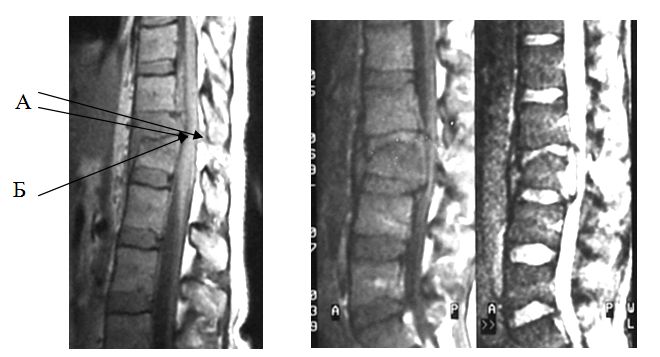

Спинной мозг при сгибательно-дистракционных (seat-belt) повреждениях, как правило, не травмирован, имеется деформация позвоночного канала без стеноза; повреждение заднего связочно-мышечного комплекса и дискового аппарата за счет дистракционного механизма травмы (рис. 8). На МРТ срезах в спинном мозге могут быть выявлены ишемические нарушения, являющиеся причиной возможных неврологических расстройств.

|

Рис. 8. МРТ признаки сгибательно-дистракционного (seat-belt) повреждения

А - зона “свечения” заднего связочно-мышечного комплекса и деформация позвоночного канала на этом уровне |

МРТ исследование при переломо-вывихах позволяет визуализировать повреждение спинного мозга и его элементов (ушиб или разрыв); стеноз позвоночного канала, компрессию дурального мешка, спинного мозга и его корешков; гемодинамические нарушения в зоне повреждения, а также нарушение целостности дискового и связочно-мышечного аппарата (рис. 9). Для переломо-вывихов характерны все перечисленные ранее “лучевые” признаки, встречающиеся при неврологических нарушениях.

Рис. 9. МРТ признаки переломо-вывиха

А – деформация и стеноз позвоночного канала Б – усиление сигнала спинного мозга в результате его сдавления или отека |